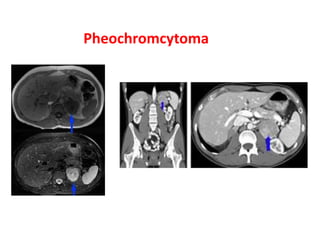

Von Hippel-Lindau disease is an autosomal dominant neurocutaneous disorder characterized by a high incidence of cysts in multiple organs and tumor development. Common manifestations include renal cell carcinoma in 25-40% of cases, cerebellar hemangioblastoma, retinal angioma, pancreatic cysts and tumors, and pheochromocytoma. Imaging findings include lesions that are intermediate to high signal on MRI and variably enhancing on CT and IVU.